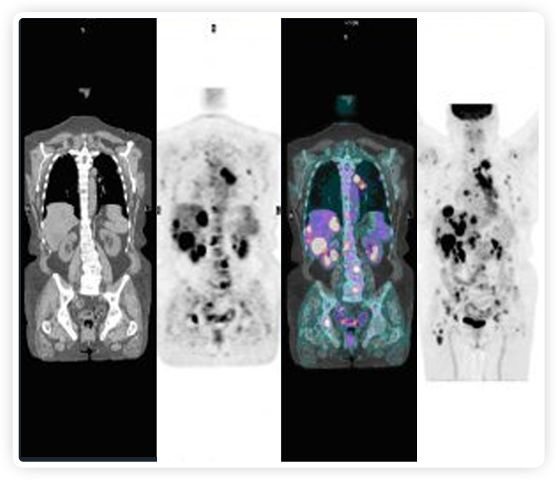

提起放療設備的引導系統,大家通常會想到結構性成像的CT或核磁。但你有沒有想過用功能性成像來引導放療呢?美國的一家醫(yī)療器械公司從2011年就致力于研究開發(fā)用PET提供生物學指導放射治療的設備BgRT。BgRT能實時利用癌癥的生物學特征作為信號指導治療全身腫瘤。

RefleXion將PET成像與立體定向放射治療相結合。在注射示蹤劑后,RefleXion的技術基于示蹤劑信號實時地在一個或多個目標上引導治療性X射線。使用這種專有方法,RefleXion的平臺有可能比現有系統向癌癥病變提供更高劑量的輻射,并改善周圍健康組織的保護。

為了避免PET長圖像采集時間,RefleXion開發(fā)了一項專利技術使用重合的PET光子對來指導放射治療束,因為實時檢測發(fā)射的光子,為生物指導提供了一種時間有效的方法。

“RefleXion系統是第一個也是唯一一個讓患者的腫瘤引導自己治療和破壞的系統,”RefleXion的創(chuàng)始人兼首席技術官Samuel Mazin博士說。“我們的目標是通過單獨治療或與免疫療法和其他晚期抗癌藥物一起消除全身疾病。我們相信這可能有助于減少世界衛(wèi)生組織預計在2030年發(fā)生的超過1300萬的全球癌癥死亡事件?!贝送?,RefleXion的技術已經被證明可以簡化和自動化放射治療過程的許多要素。